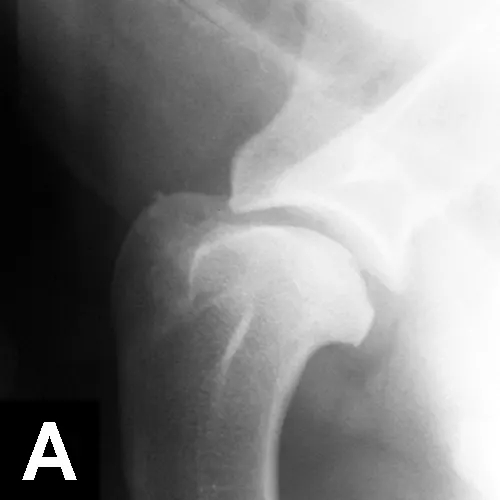

Mediolateral radiographs of the shoulder in an 8-month-old German short-haired pointer with left forelimb lameness. Flattening of the humeral head with sclerosis of the underlying subchondral bone suggests OCD.

Large-breed dogs are most commonly affected, usually presenting with unilateral or bilateral forelimb lameness between 4 and 8 months of age. Muscle atrophy and pain during shoulder manipulation may be found in affected dogs. Diagnosis is based on clinical signs and radiographic visualization of flattening of the caudal aspect of the humeral head (Figure 10A). Positive-contrast arthrography may help in the diagnosis when radiographs are unclear (Figure 10B). Advanced imaging (eg, CT, MRI) can be helpful in elusive cases.Surgical or arthroscopic removal of the cartilage flap with debridement of the subchondral bone often leads to an excellent prognosis (Figure 10C).